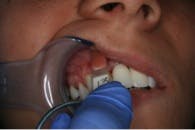

Due to the patient’s age at the time of trauma, the crowns were replaced five years later with lava crowns, which are porcelain crowns with a zirconia framework inside (refer to figure 2a and 2b).

One year after the crowns were replaced, the teeth became mobile. The patient went in for an appointment and radiographs confirmed external root resorption had occured around the reimplanted teeth (refer to figure 3).